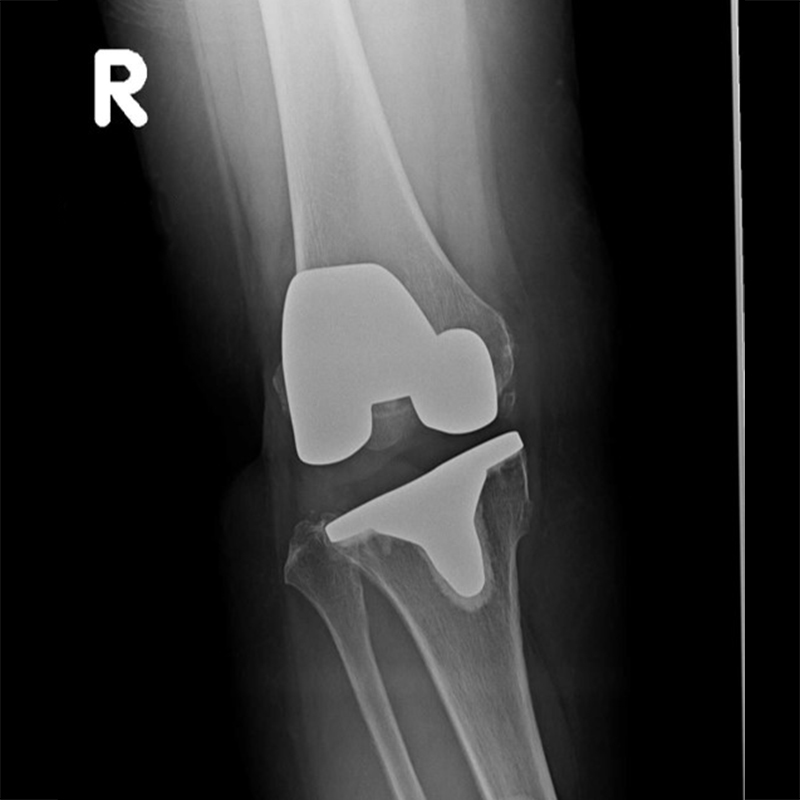

外院失敗本院再置換 首頁 案例分享 膝關節手術 外院失敗本院再置換 蕭女士 69歲 術前 術後 81歲 林女士 術前 術後 蕭女士 69歲 術前 術後 鄒女士 69歲 術前 術後 李女士 74歲 術前 術後 吳女士 71歲 術前 術後 謝女士 65歲 術前 術後